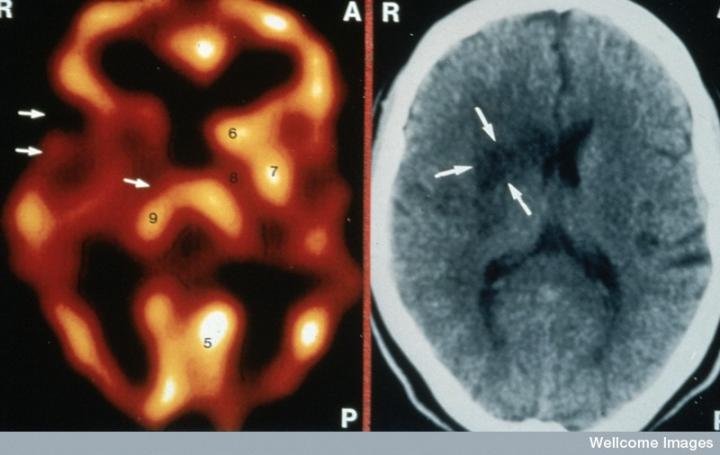

左側的血流圖比右側的X射線CT掃描顯示出更多的中風損傷

慢性中風患者的腦成像

CT掃描的主圖顯示左側有一些中風損傷,由 Wellcome Images提供。Wellcome Photo Library提供的慢性中風的附加圖像 ,Wellcome Images,QL 從胚胎干細胞培養的神經元。Ying & A. Smith, Wellcome Images 和 Yirui Sun, Wellcome Images 移植的小鼠神經干細胞。